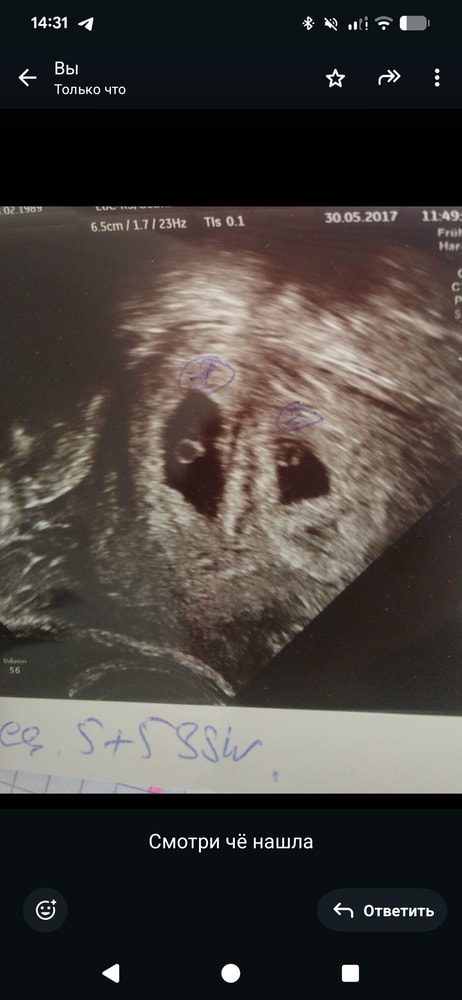

Девочки у кого двойни или те кто сталкивался с подобной ситуацией. У меня ровно 6 недель, была на УЗИ, врач сказала что не понимает там один или два эмбриона, срок маленький и записала через 20 дней повторно. Ни на один мой вопрос не ответила, сердце не слушали, она сказала рано. А у меня вопросов сотня, но первый как это не понятно один или два? Разве такое бывает? Что на бОльшем сроке может оказаться два эмбриона? Или как вообще это понять можно?? Не пишите пожалуйста о походе к другому врачу или клинику, в Европе это анриал даже платно. Радует что следующий раз врач будет уже другой, но записи раньше не будет. У кого так было что точно видели одного эмбриона, а второй был под вопросом? И в итоге сколько родилось детей 1 или 2?

У меня двойня.. на 5+5 SSW все было видно.. сильно не переживайте, мож действительно рано ещё.